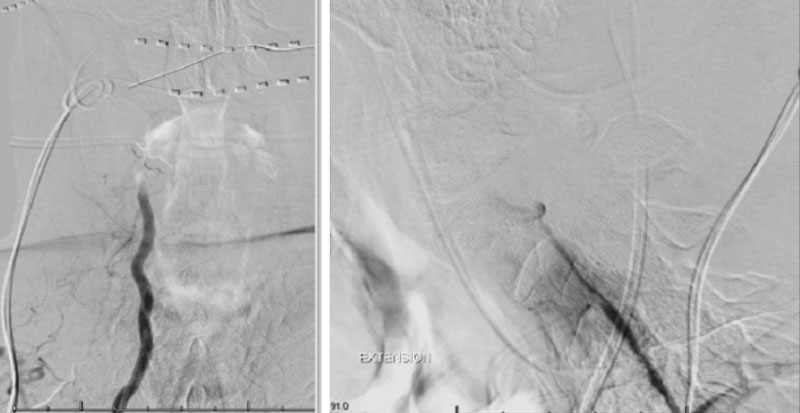

During neutral positioning, the vertebrobasilar circulation fills briskly from the Right Vertebral Artery. (Figure 4)

On rotation to the left, the patient experienced mild symptoms, however no significant Vertebral Artery or basilar reduction in flow was observed. On rotation to the right, the patient experiences slightly more moderate symptoms, however no significant Vertebral Artery or vascular reduction flow was observed. On hyper extension of approximately 10-15 degrees, passively performed by the patient until symptoms are reproduced, angiogram demonstrates complete occlusion of the right Vertebral Artery at approximately the C2-C1 level. (Figure 5)